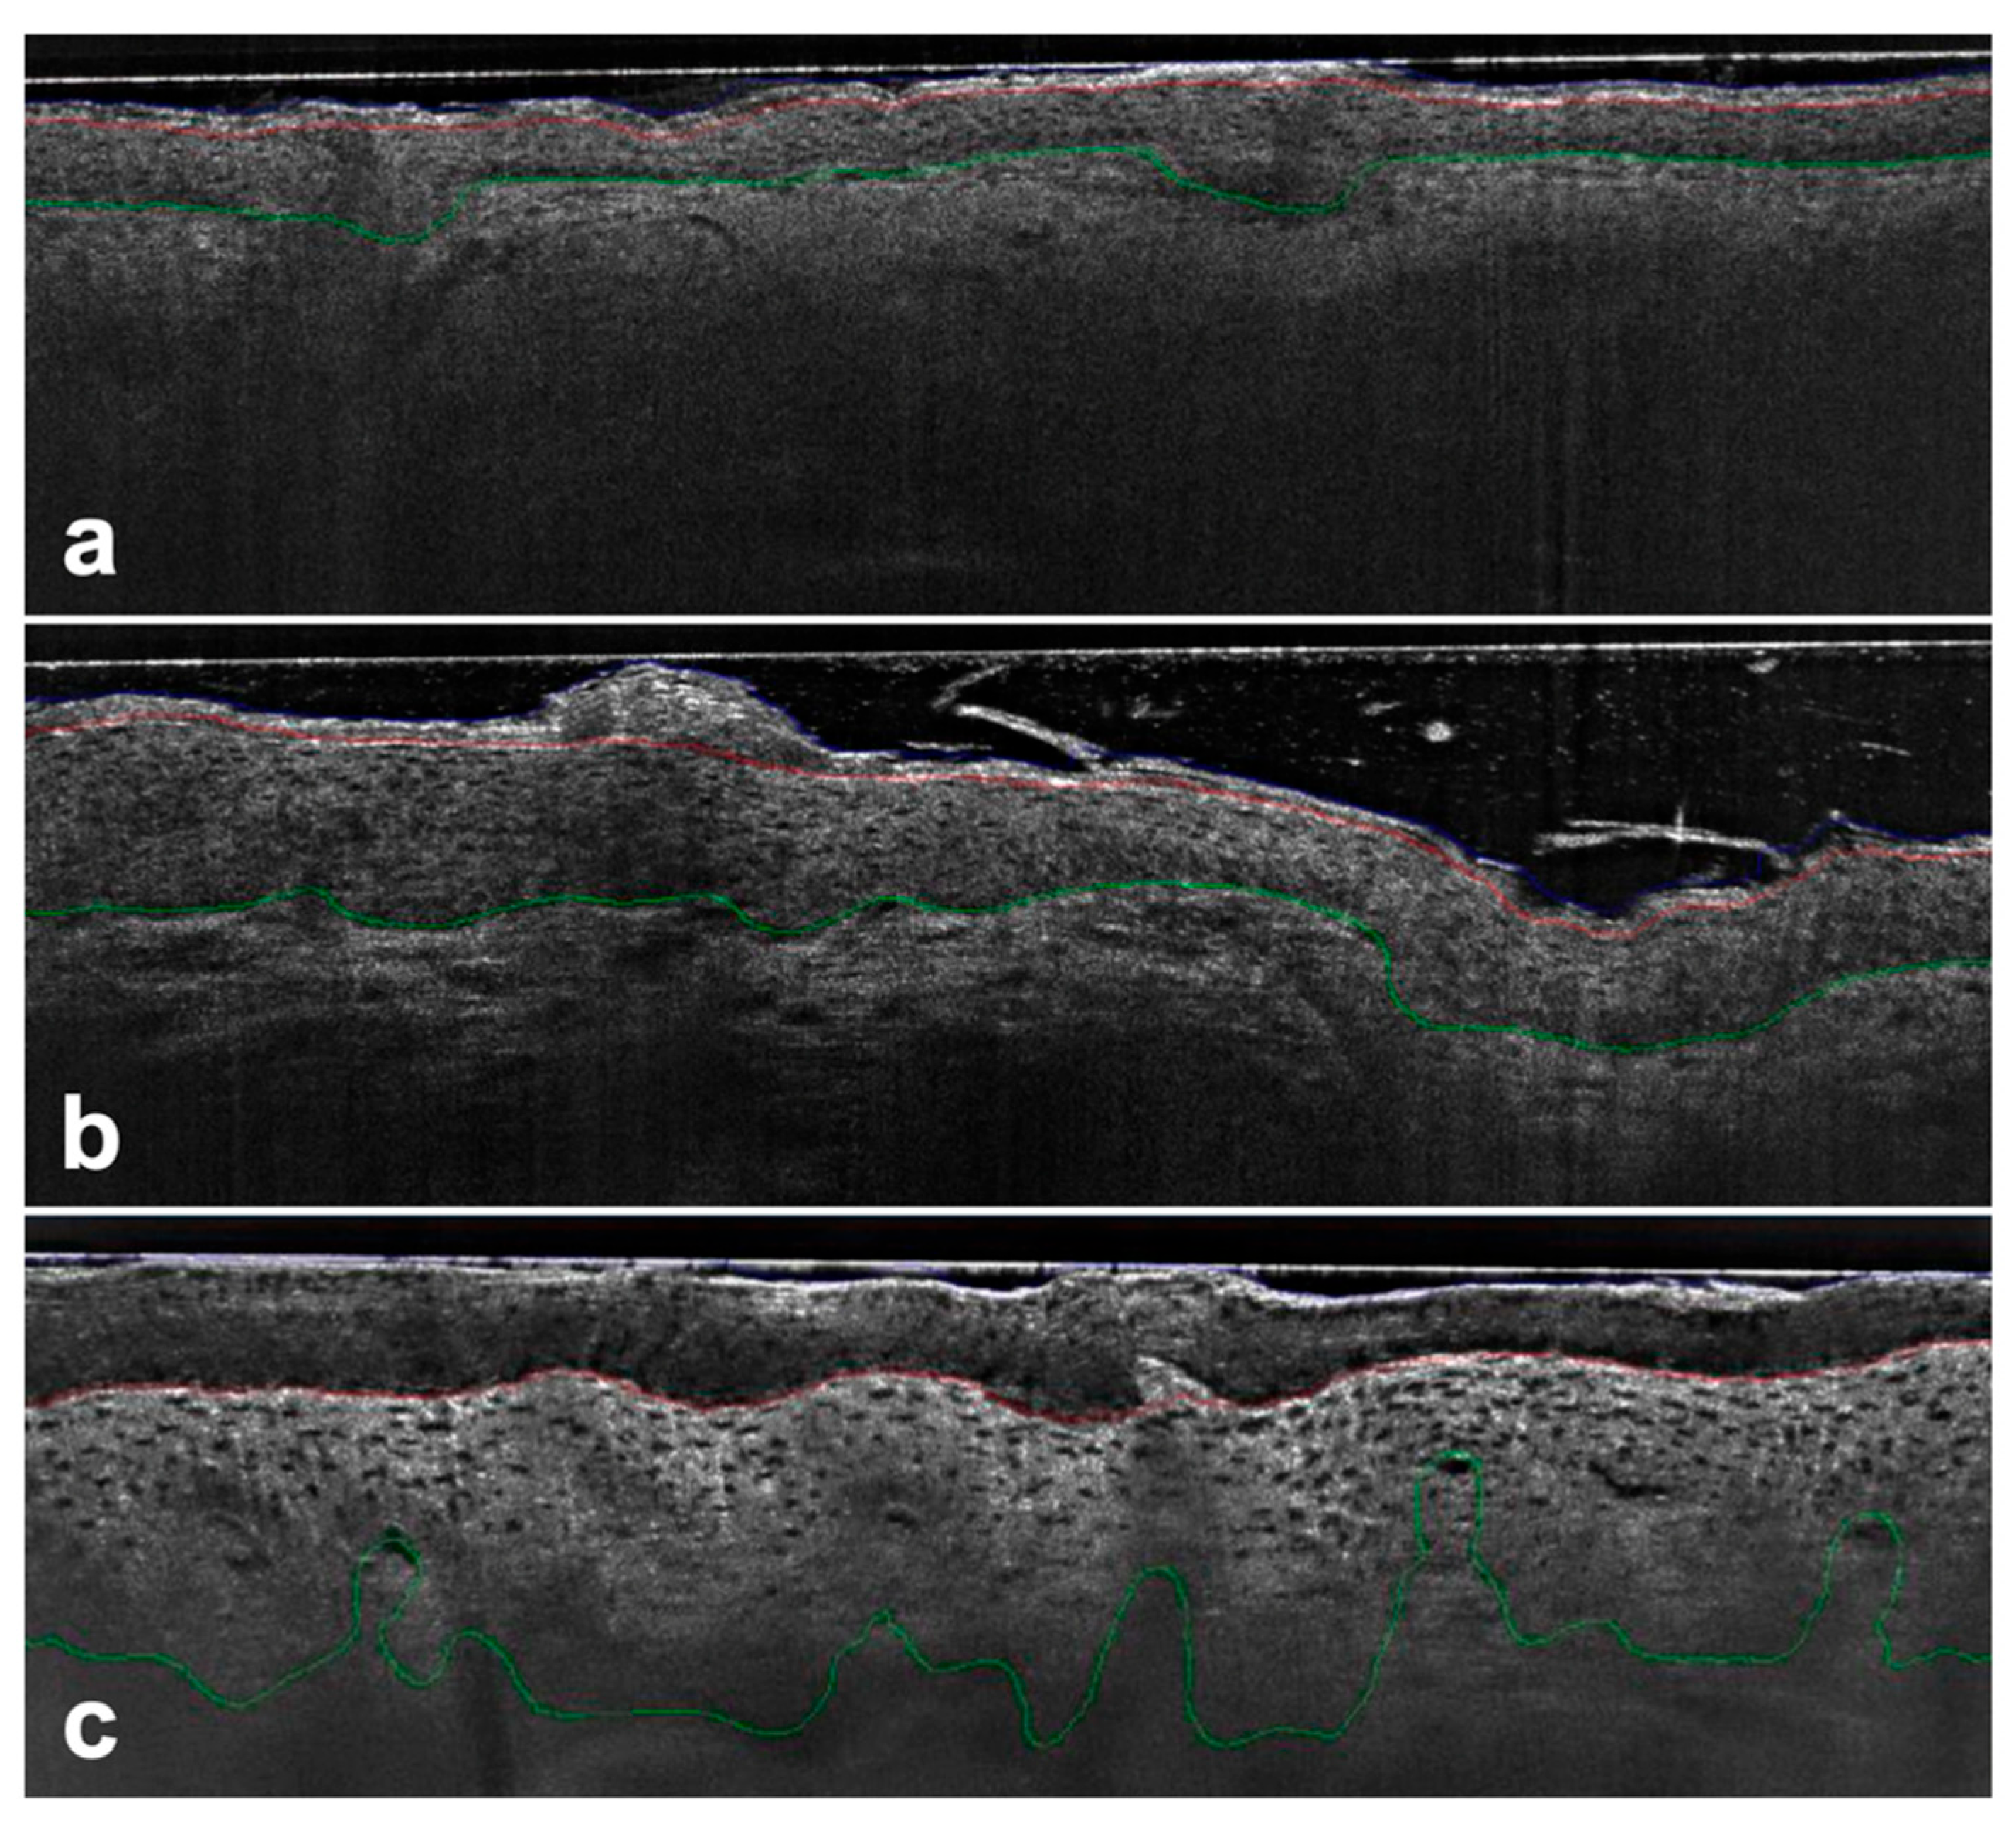

To address this limitation and considering that the interaction between the epidermis and dermis, along with tumor invasiveness, originates at the dermoepidermal junction zone, a histomorphological classification based on the basal growth pattern (PRO I–III) of atypical keratinocytes has been proposed [9]. The PRO score is a widely used clinical scoring system for AK-based histological findings at the DEJ [10]. While early-stage PRO I is characterized by clustered and atypical keratinocytes in basal epidermal layers, PRO II shows how small hemispherical buds from the basal epidermis slightly protrude into the upper papillary dermis. In PRO III, we can see spiky or filiform papillary elongations of atypical keratinocytes protrude into the upper dermis [10,11].

Protrusions were detected by comparing the position of the DEJ with a reference estimate of the flat DEJ position. The skin surface was used as an estimate offset by the average thickness of the epidermis. Areas with DEJ below the estimated value were classified as protrusions. Once these regions were identified, the ledge width was quantified as the distance between two intersections where DEJ crossed the estimator.

For each of the 19,898 images analyzed, the undulation of the DEJ, the number of protrusions, and the maximum depth of the protrusion were computed. These metrics were then averaged at the lesion level. The undulation of DEJ was expressed as the length of the DEJ contour divided by the length of the imaged area in a straight line, while undulation depth was calculated as the difference between the highest and lowest points of the DEJ within the interval described by the two intersection points plus a small margin of 10 μm (see Figure 1).

Figure 1. AK PRO score assessment in vertical LC-OCT images (DeepLive, DAMAE Medical, Paris, France) image size: 1.2 × 0.5 mm2, lateral and axial resolution: 1.1 μm × 1.3 μm—Protrusions were detected by comparing the position of the DEJ (green line) to a reference estimator in the upper epidermis (red line) with no protrusions detected using the algorithm for PRO I (a), while for PRO II (b) and PRO III (c) the basal epidermis protruded progressively into the dermis.